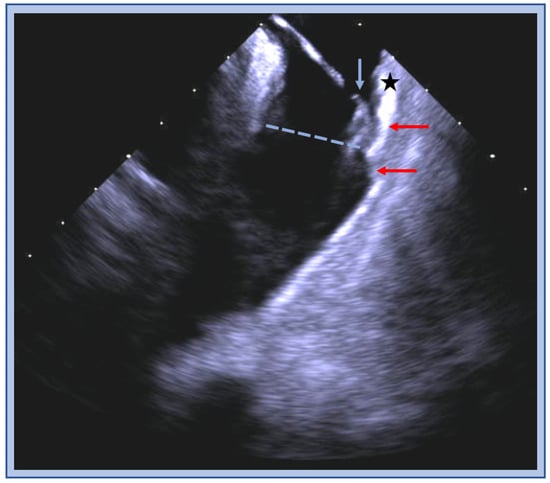

6. Moderator Band VT

6.1. ECG Signatures

6.2. Catheter Ablation